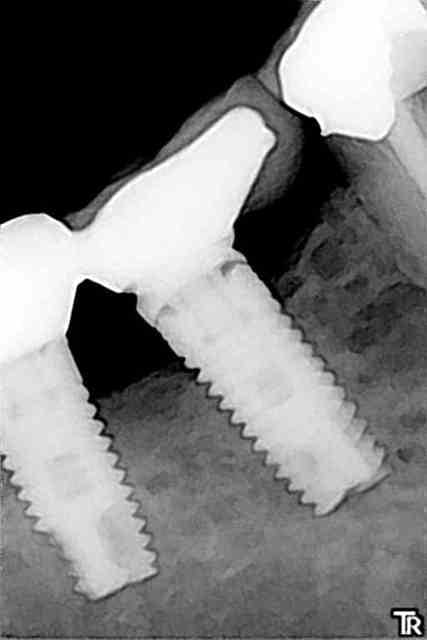

J'ai cette petite série de cliché.

Pour préciser je n'ai aucun problème d'hygiène, d'occlusion....ou autres chez cette patiente et cependant ça a donné ceci.

Je vois régulièrement la dame mais elle ne souhaite pas que je sépare et dépose l'implant à problème malgré toutes les explications que j'ai pu lui donner.

La hauteur gingivale est ok sur les deux implants malgré une légère inflammation inconstante sur le problématique...

Édit: Lire décembre 2011 sur la dernière radio bien sur ^^